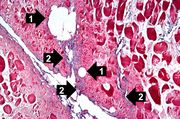

| 04:03, 21 August 2013 | IPLab10Candidiasis6.jpg (file) | 78 KB | This high-power photomicrograph shows the yeasts (1) and pseudohyphae (2). | 1 | |